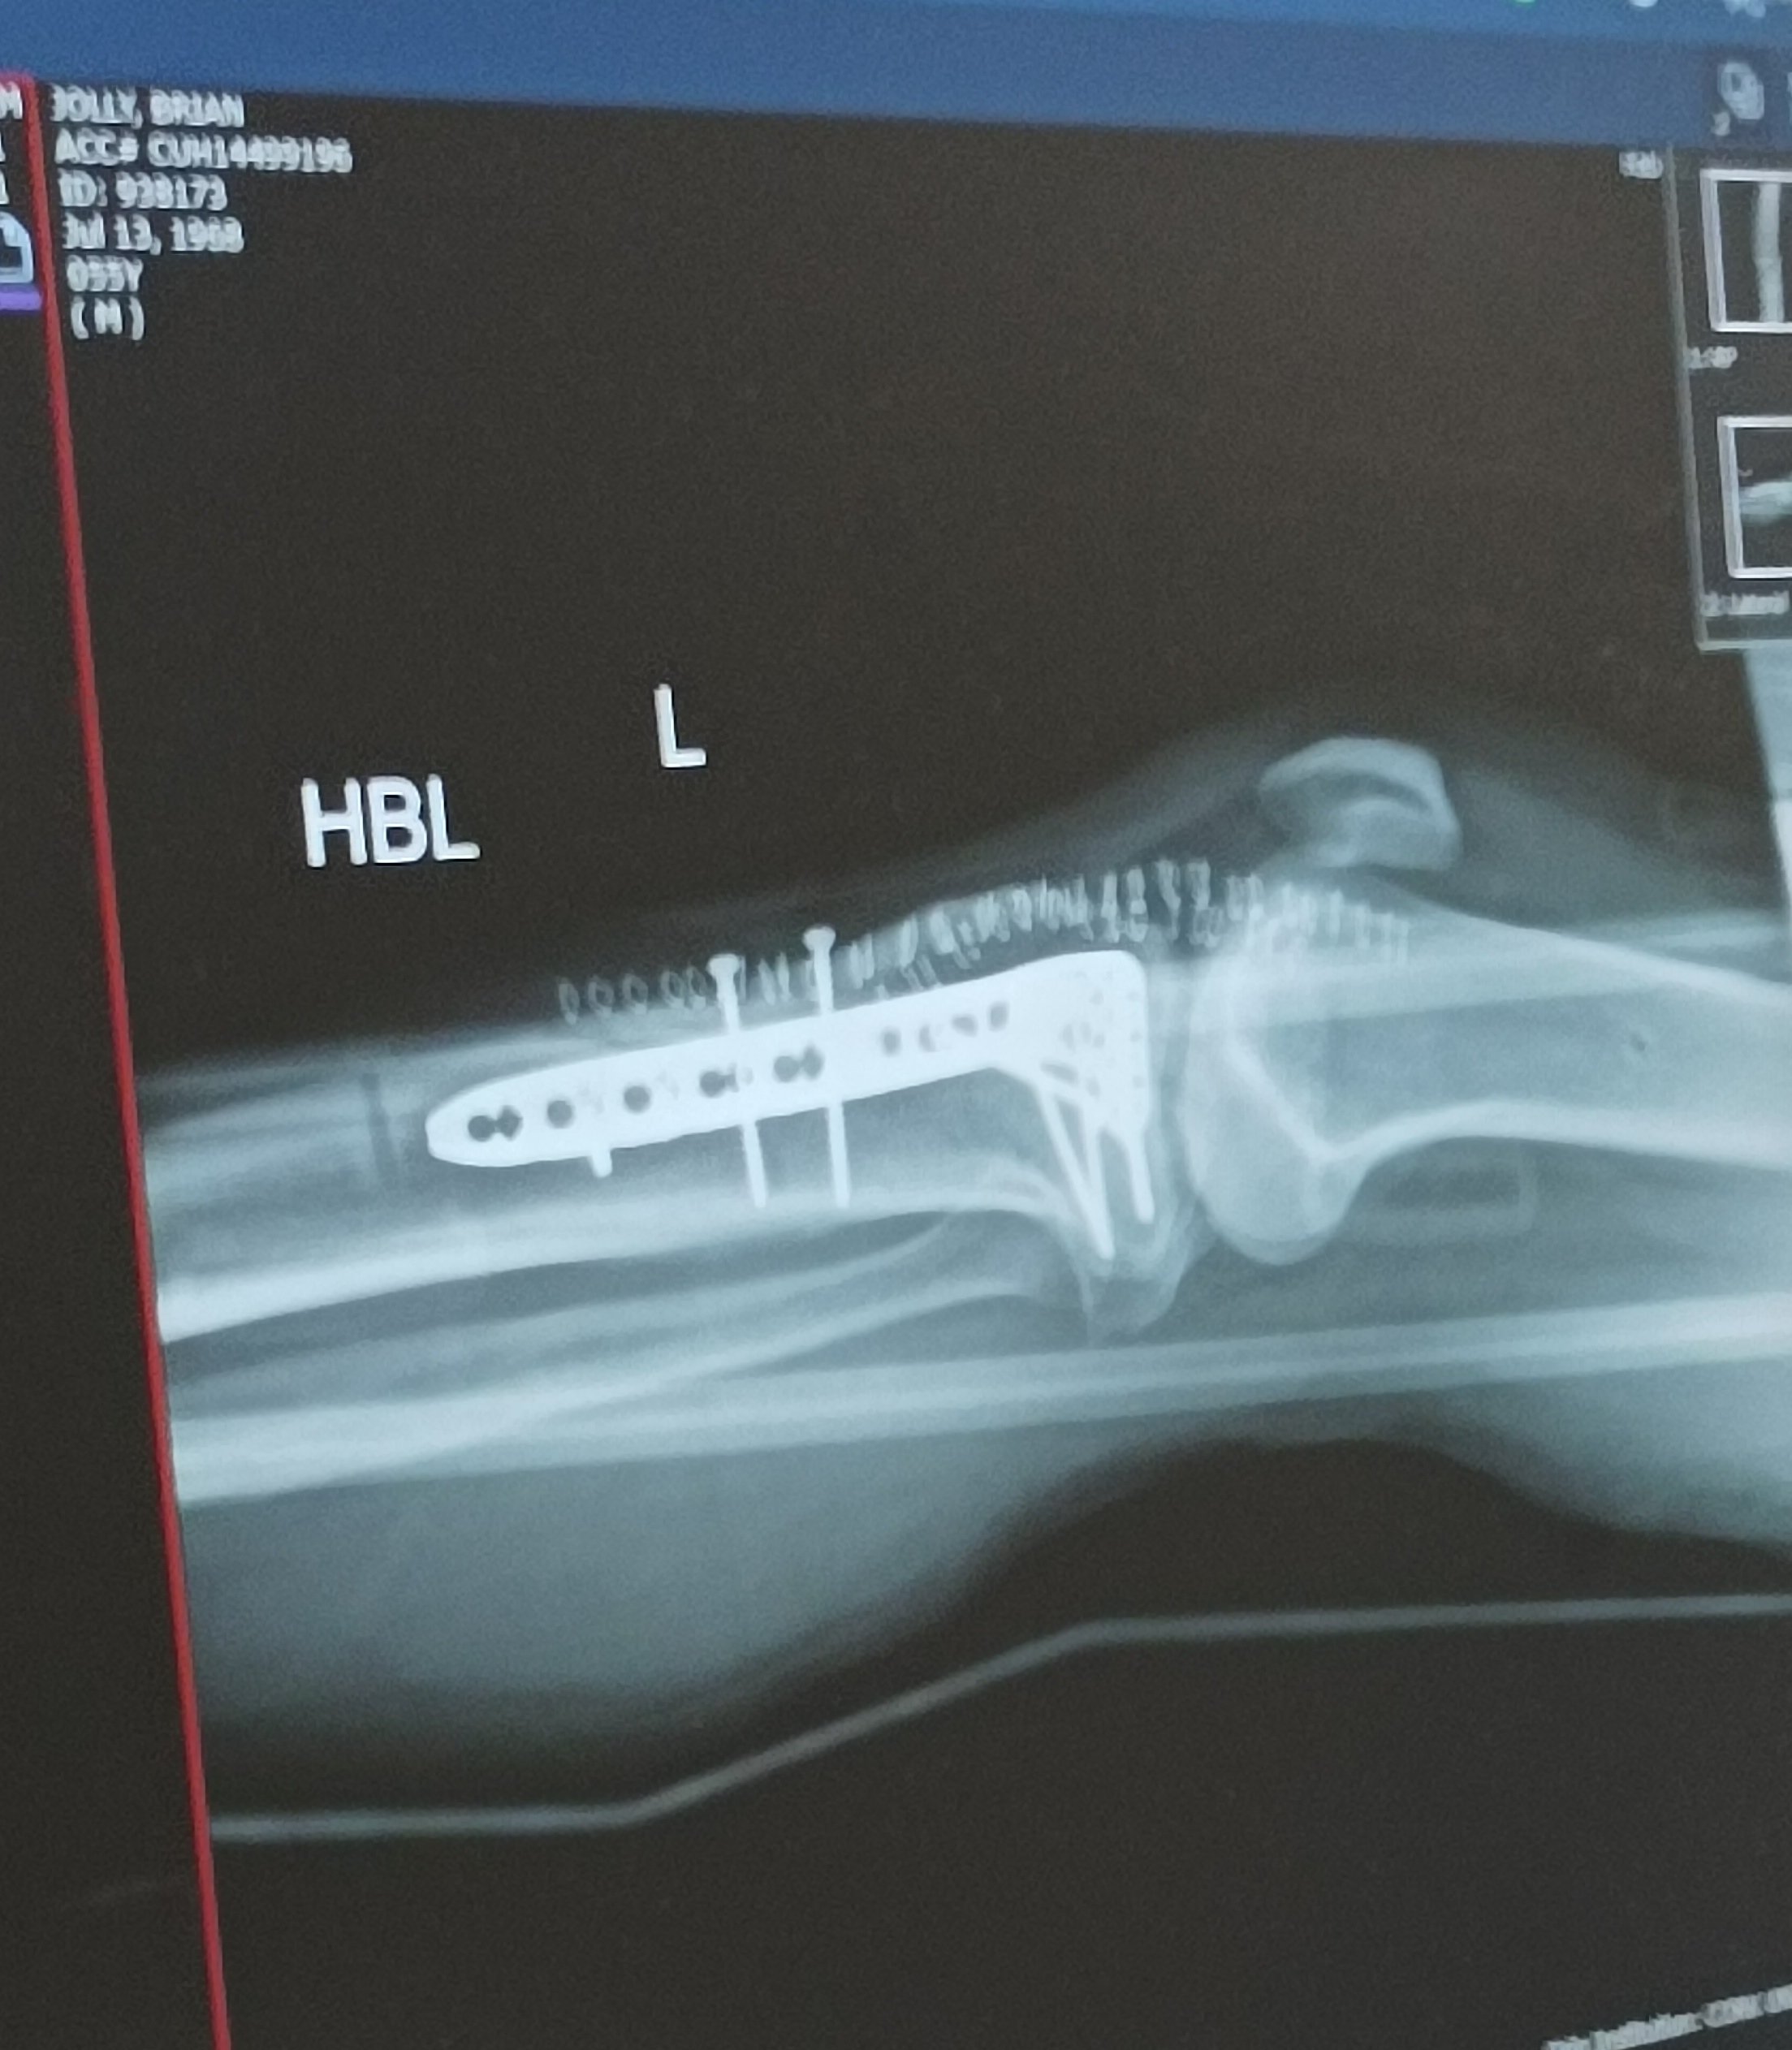

So I'm guessing, OF watercooler, a place to shoot the shit kinda thing😀, so questions, anybody got any metal in them?

I took a bit of a tumble 3 weeks ago while skiing, ended up with this, left tibia fractures.

Anybody got something similar, how did it work out? I'm all good, just need to be patient now, fortunately time I have so one day at a time.

Thanks, it's titanium, and my understanding is that it will stay in, until I need a new knee, 10 to 15 years. Fortunately no real pain, just uncomfortable, I'm lucky.

Had something similar about 6 years ago. Worked out OK. Some nerve damage so loss of feeling down front of leg and some reduction in flexibility but all in all a success story.

Follow all the guidelines and do exactly as advised